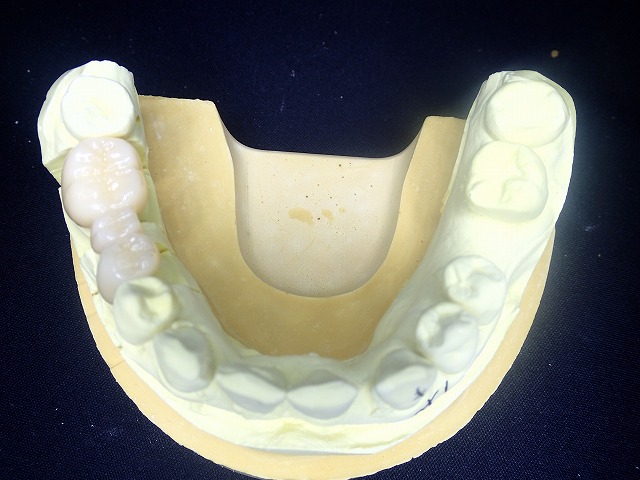

技工物完成 奥歯で咬む位置を設定した状態で

技工物にも計測した

水平 垂直が写して

描記してありますが、実際にお口装着すると

多少のズレがありますので、お口の中で

ジルコニアの形態を修正します。

マルチレイヤージルコニア

先端は白く透明

歯頚部は色が濃く

天然の歯のようにグラデーションがあります。